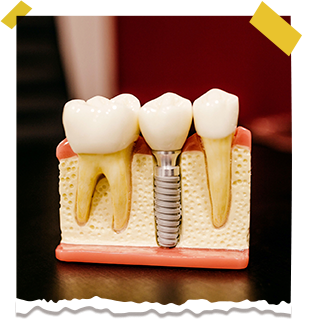

روشی که در آن پایه ای فلزی در استخوان فک قرار می گیرد و روی این پایه، تاج دندان مصنوعی نصب می شود تا عملکرد و ظاهر دندان طبیعی را بازگرداند.